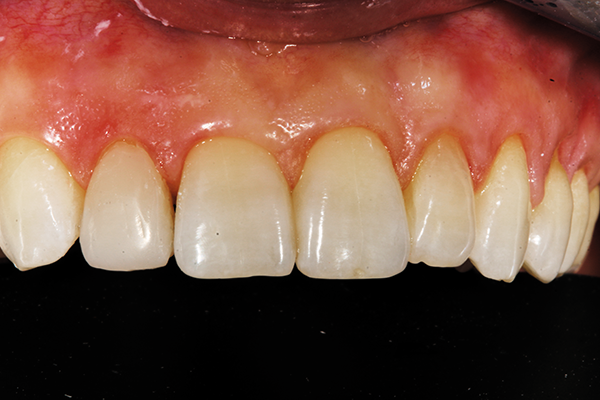

Interproximal polishing was done with various grits of strips to aid in flossing and to decrease the risk of stain buildup in the future (Fig. 11). ALPEN® ShapeGuard™ Composite Plus Step 2 Polishers and a felt polishing disc with aluminum oxide paste created a natural high gloss finish for esthetics and longevity (Fig. 12).

Fig. 12 Fig. 13

The close-up, post-treatment photo demonstrates the beautiful blend of color and anatomical congruency for this minimal change to the patient’s smile (Fig. 13). The patient was ecstatic about the simple and natural improvement in her appearance - especially doing this with no anesthesia given her heart condition. It was gratifying to help this young mother feel more confident again. The transitional approach with a very reliable composite could be a stepping stone for our patient’s desire for an ideal smile when her medical condition stabilizes. (Fig. 14).